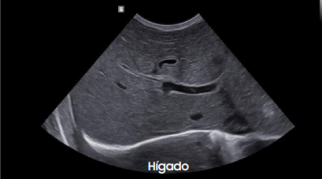

Galería de imágenes